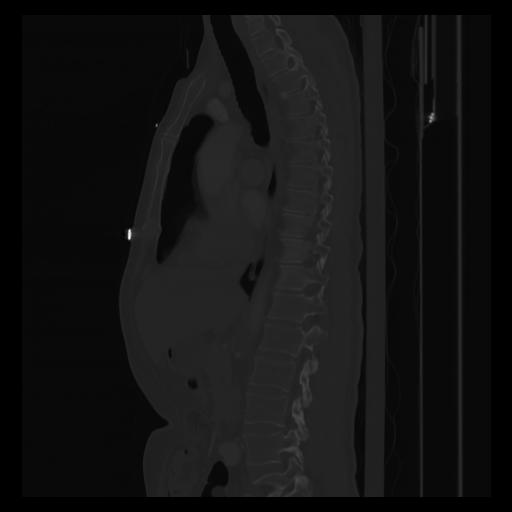

30 CUERPO,CE,Sagittal,3.000,CUERPO,Sagittal,